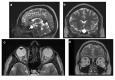

Results: Seventy-nine patients were diagnosed with IIH. Bilateral transverse sinus stenosis (TSS) was found in 74% of the population. Visual outcome at 6 months was poor for 46% of patients, including all patients presenting weight gain of at least 5% since diagnosis (p < 0.001), whereas mean body mass index at diagnosis was not different between patients with poor versus good outcome (32.9 ± 7.7 versus 34.6 ± 9.4 kg·m-2). Other significant factors of poor prognosis were bilateral TSS (OR = 5.2; 95 CI: 1.24-24.9; p = 0.024). Thirteen patients with poor outcome after 6-month assessment underwent unilateral TSS stenting leading to visual improvement in 11 cases.

Conclusion: Weight gain, rather than initial weight, emerged as the leading factor of poor visual outcome in patients with IIH, followed by presence of bilateral TSS. Consequently, first-line treatment must include dietary measures to control weight. Unilateral stenting appears to be a safe second-line treatment option for patients with bilateral TSS.